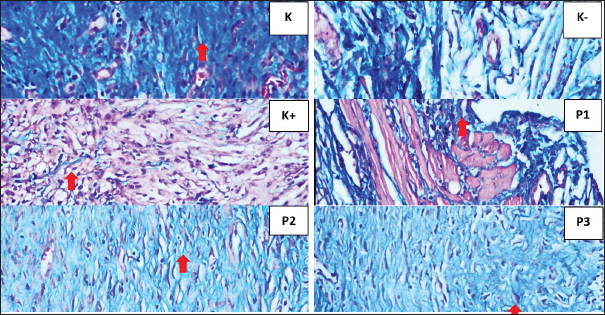

The lowest IL-10 levels were observed in the 50% P. crocatum extract gel group=247,515. The lowest TGF-B1 expression observed in the 25% P. crocatum extract gel group=4,033. The highest VEGF expression was observed in the 25% P. crocatum extract gel group=11.45. The highest collagen density was found in the 50% Piper crocatum extract gel group=0.833, and the smallest percentage of wound area approaching normal wounds was in the 50% P. crocatum extract gel group, which was 11,338 (Fig. 1). TGF-β1 expression is shown as brown color in rat skin (Rattus norvegicus), seen in the 50% P. crocatum extract gel group (P3), with the lowest value=4 (Fig. 2). Based on IHC examination using Santa Cruz antibodies, the VEGF expression was observed in large blood vessels with brown endothelium visible in the skin of rats in the 25% P. crocatum extract gel group (P2), with the highest number 13 (Fig. 3). The group with the highest collagen density was the 50% P. crocatum extract gel (P3)=0.833 (Fig. 4). The group with wound healing approaching normal wounds was the 50% P. crocatum extract gel group (P3) even though almost all of them were diagnosed with malignant tumors (Figs. 5 and 6). Path analysis of the direct and indirect effects of P. crocatum extract (Fig. 7) and mechanism of effect of P. crocatum extract on IL-10 levels, TGF-β1 expression, VEGF expression, and collagen density in post-excision wounds of mammary tumors of female Wistar rats (Fig. 8).

Fig. 3. Histopathological features of Wistar rat skin post-excision of mammary tumor after treatment for 14 days in each group. VEGF expression shown in endothelial cells (⇧) in figure K (5.3), K- (6.1), K+ (8.5), P1 (7.5), P2 (13), and P3 (5.9) (HE staining, magnification of 400).

Fig. 4. Histopathological features of Wistar rat skin post-excision of mammary tumors after treatment for 14 days in each group, as indicated by collagen (⇧) K (scoring 3) K- (scoring 0), K+ (scoring 1), P1 (scoring 2), P2 (scoring 1), and P3 (scoring 3) (HE staining, magnification of 400×).